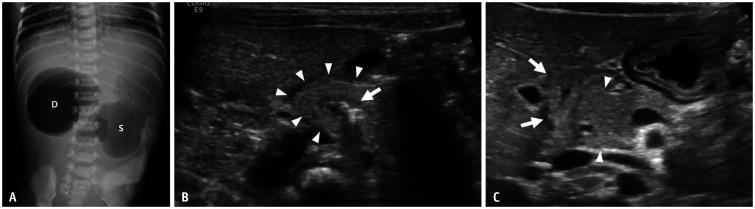

Gastrointestinal (GI) emergencies in neonates and infants encompass from the beginning to the end of the GI tract. Both congenital and acquired conditions can cause various GI emergencies in neonates and infants. Given the overlapping or nonspecific clinical findings of many different neonatal and infantile GI emergencies and the unique characteristics of this age group, appropriate imaging is key to accurate and timely diagnosis while avoiding unnecessary radiation hazard and medical costs. In this paper, we discuss the radiological findings of essential neonatal and infantile GI emergencies, including esophageal atresia and tracheoesophageal fistula, hypertrophic pyloric stenosis, duodenal atresia, malrotation, midgut volvulus for upper GI emergencies, and jejunoileal atresia, meconium ileus, meconium plug syndrome, meconium peritonitis, Hirschsprung disease, anorectal malformation, necrotizing enterocolitis, and intussusception for lower GI emergencies.

新生儿和婴儿的胃肠道(GI)急症涵盖了从胃肠道的开始到结束的各个方面。先天性和后天性疾病都可能导致新生儿和婴儿出现各种胃肠道急症。鉴于许多不同的新生儿和婴儿胃肠道急症的临床发现具有重叠或非特异性,以及该年龄段的独特特征,适当的影像学检查对于准确和及时的诊断至关重要,同时避免不必要的辐射危害和医疗费用。在本文中,我们讨论了基本的新生儿和婴儿胃肠道急症的放射学表现,包括食管闭锁和食管气管瘘、肥厚性幽门狭窄、十二指肠闭锁、肠旋转不良、胃上消化道急症,以及空肠回肠闭锁、胎粪性肠梗阻、胎粪栓综合征、胎粪性腹膜炎、先天性巨结肠、肛门直肠畸形、坏死性小肠结肠炎和肠套叠等下消化道急症。